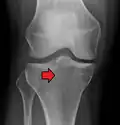

Subtle tibial plateau fracture on an AP X ray of the knee -

A tibial plateau fracture seen on X-ray

In all injuries to the tibial plateau radiographs (commonly called x-rays) are imperative. Computed tomography scans are not always necessary but are sometimes critical for evaluating degree of fracture and determining a treatment plan that would not be possible with plain radiographs.[10] Magnetic Resonance images are the diagnostic modality of choice when meniscal, ligamentous and soft tissue injuries are suspected.[11][12] CT angiography should be considered if there is alteration of the distal pulses or concern about arterial injury.